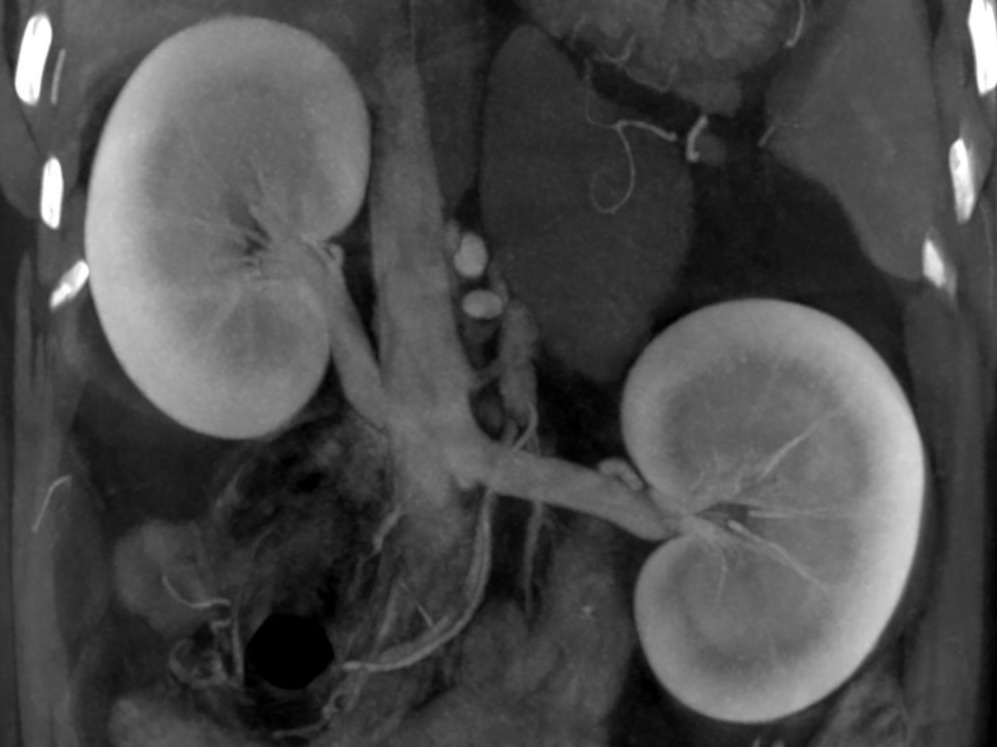

CT

Abdominal CT of Kidneys